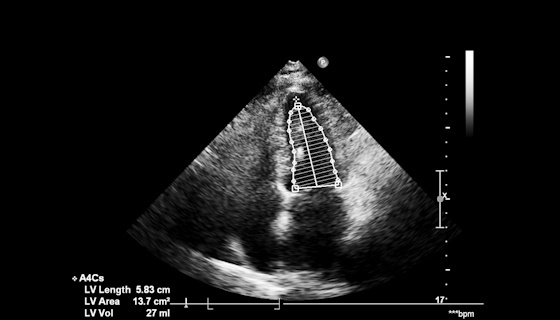

Évaluation hémodynamique échographique dans l’insuffisance cardiaque